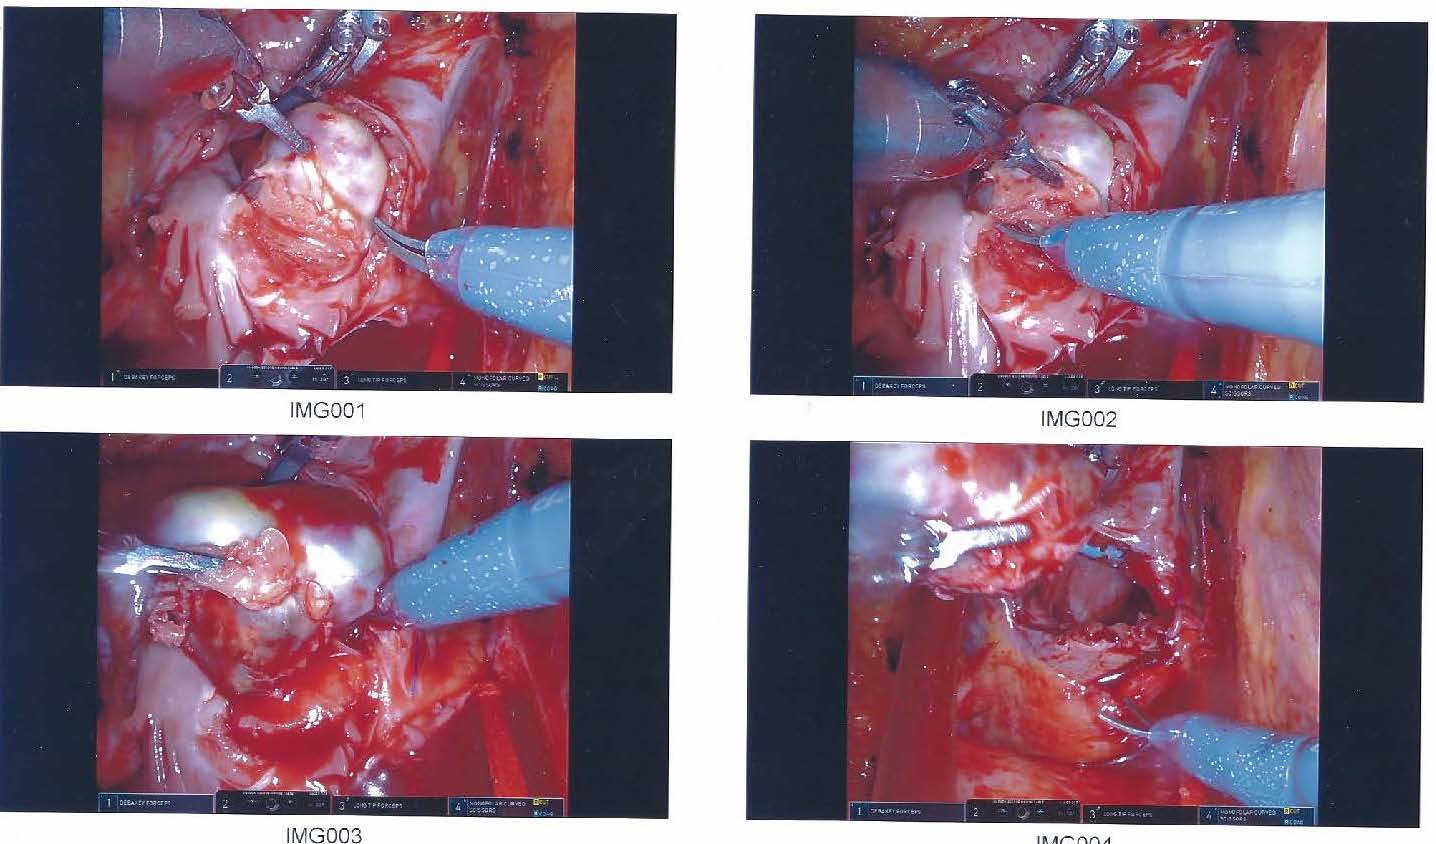

In September 2018, approximately 9 months after initial presentation, the patient underwent surgical removal of the atrial myxoma near the interatrial septum proximate to the venous septum and right atrial junction via minimally invasive thoracic robotic surgery (Figure 2). A large egg- to peach-sized mass was sent for pathology testing, the results of which confirmed the diagnosis of benign atrial myxoma with fibrosis, calcification, and ossification (Figure 3).

Figure 2. Right atrial myxoma located intraoperatively near the venous septum and right atrial junction.

Figure 3. Right atrial myxoma, described as the size of a small peach by the cardiothoracic surgeon.